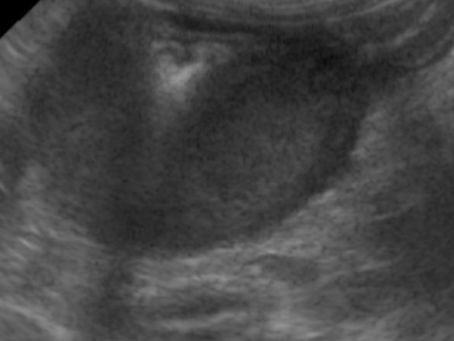

Colonic mast cell tumour in a cat

A cat was referred for an abdominal ultrasound following the palpation of a potential mass during a routine abdominal examination. The...